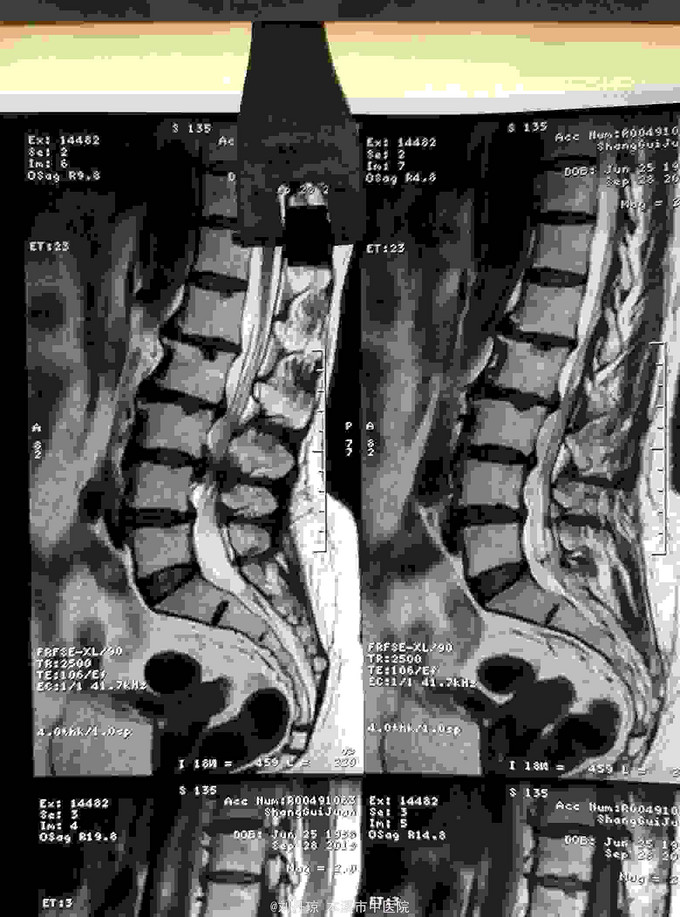

腰部疼痛伴右下肢放射痛麻木感半年,加重2月。患者半年前劳累后感到腰部疼痛伴右下肢放射痛麻木感,近2月病情加重来诊。

查体:L1—S1棘突右旁压痛阳性。直腿抬高实验左70度,右40度。 直腿抬高加强实验左侧阴性,右侧阳性。腰椎功能障碍。 辅查:CT: L1—S1椎间盘突出。

诊断:腰椎间盘突出症 治疗:针灸、雷火灸、中药熏药治疗、小针刀治疗、骶管注射治疗、营养神经药物治疗、脱水药物治疗,当归地黄饮加味。